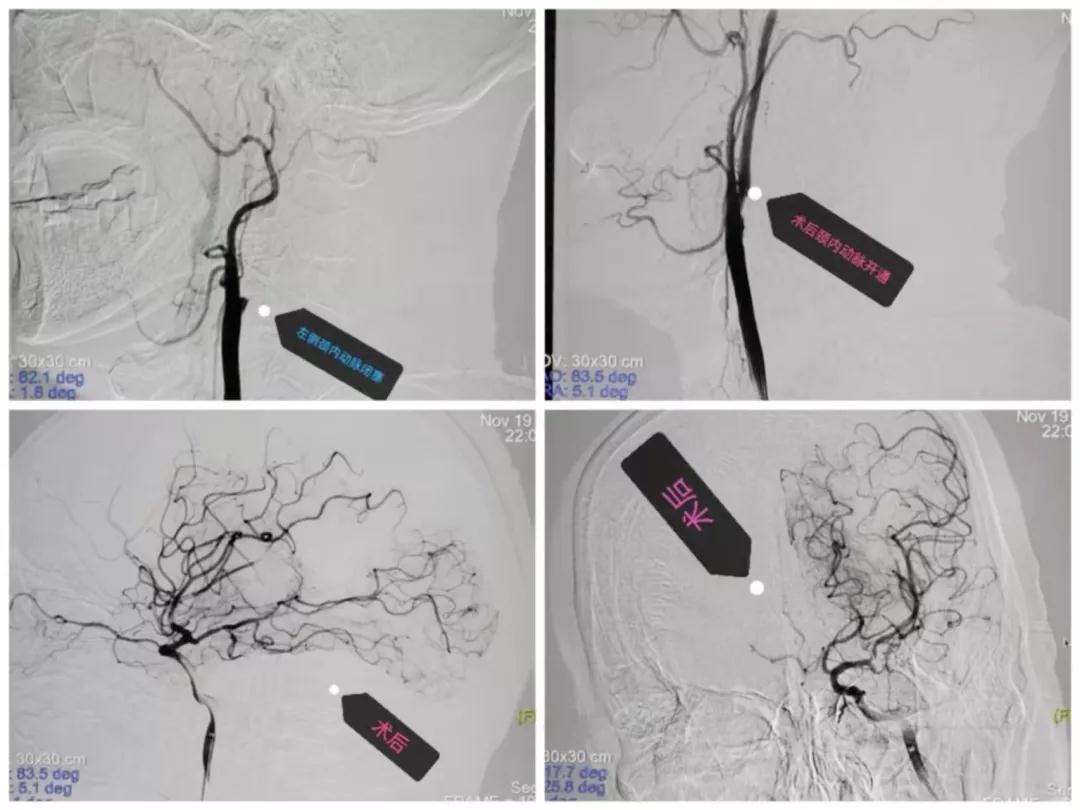

开展了第一例脑血管造影术,为脑血管病患者提供清晰、精准的治疗,全年共开展脑血管造影术260余台次。

介入团队完成了第一例颅内血管动静脉畸形栓塞术,打响了脑血管病介入治疗的“第一枪”。

开展第一例急性脑血栓支架取栓术,全年共开展取栓术11例。

开展颅内动脉瘤介入栓塞术15例,为患者及时拆除脑内“不定时炸弹”,为患者生命健康保驾护航。